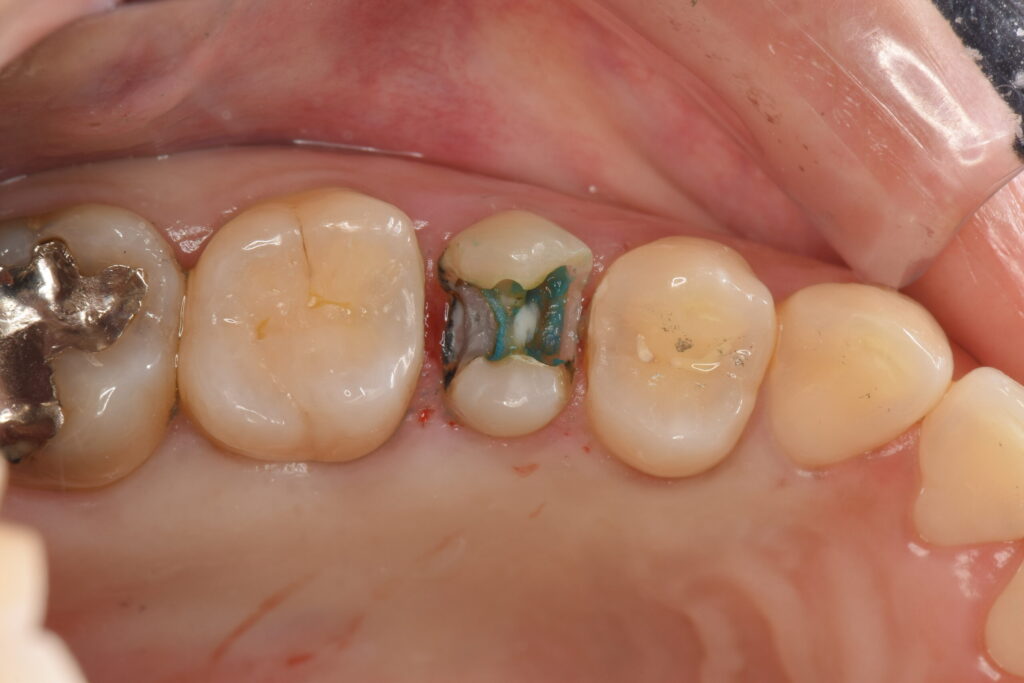

虫歯が青く染まる「カリエスチェッカー」を用いたところ、奥の方にも虫歯が進行していることが分かりました。

ラバーダム防湿下で虫歯を丁寧に除去し、VPT治療(歯髄温存療法)を行なっていきます。